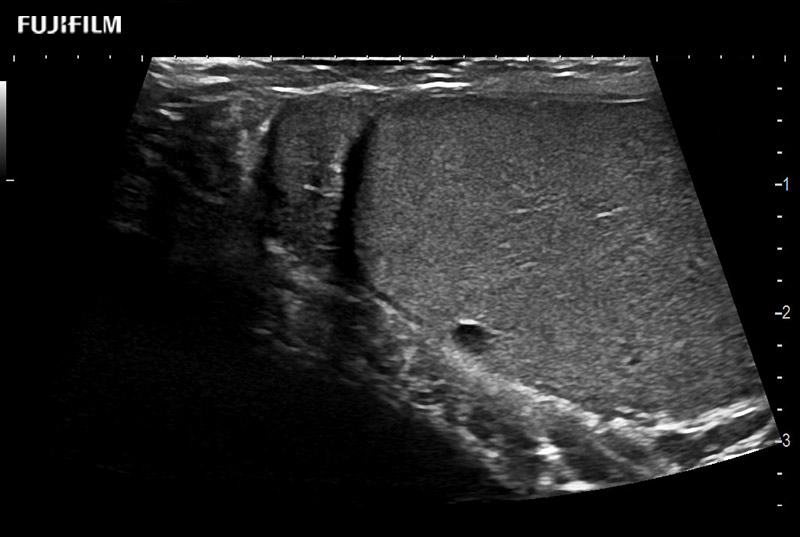

Abdominal transducer for biopsy, bladder and renal applications.